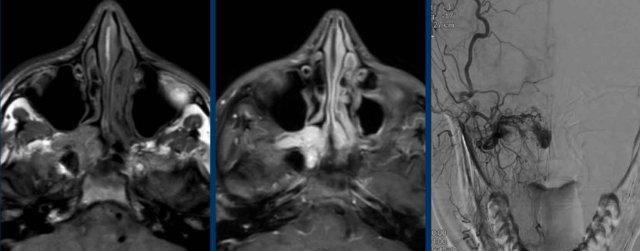

U cơ vân (Rhabdomyosarcoma)

Các hình ảnh này của một bệnh nhân nam 16 tuổi với biểu hiện lồi mắt và chảy máu mũi.

Dựa trên kết quả CT tại bệnh viện khác, có nghi ngờ u xơ mạch máu vị thành niên (juvenile angiofibroma) — một khối u tăng sinh mạch máu, xâm lấn tại chỗ, gặp ở nam giới trẻ tuổi với biểu hiện chảy máu mũi nặng, có thể đe dọa tính mạng.

Trên các hình ảnh này, có một tổn thương phá hủy xương với xâm lấn vào hốc mắt.

U xơ mạch máu vị thành niên luôn xuất phát từ hốc mũi phía sau và có tâm tổn thương xung quanh lỗ bướm khẩu cái và hố chân bướm khẩu cái.

Tiếp tục xem các hình ảnh MRI…

MRI cho thấy một khối u phá hủy một bên với hạn chế khuếch tán rõ rệt (giảm tín hiệu trên bản đồ ADC).

Như vậy, chúng ta có ba dấu hiệu cảnh báo.

Hạn chế khuếch tán là một lập luận khác chống lại chẩn đoán u xơ mạch máu vị thành niên, vì một tổn thương mạch máu sẽ không gây ra hạn chế khuếch tán.

Có xâm lấn vào hốc mắt và cả vào phần mềm phía trước của má (mũi tên).

Sinh thiết được thực hiện và cho kết quả là u cơ vân (rhabdomyosarcoma), được điều trị bằng hóa trị liệu.